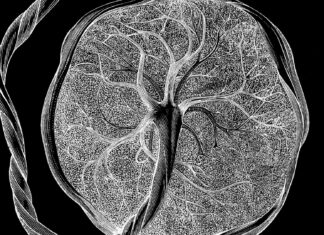

Подвійний охоронець кишечника: як білок інтелектин-2 захищає організм від інфекцій

Нове дослідження, проведене вченими з Массачусетського технологічного інституту (MIT), виявило складну біологічну систему безпеки в травному тракті людини. Дослідження показує, що специфічний білок, відомий...